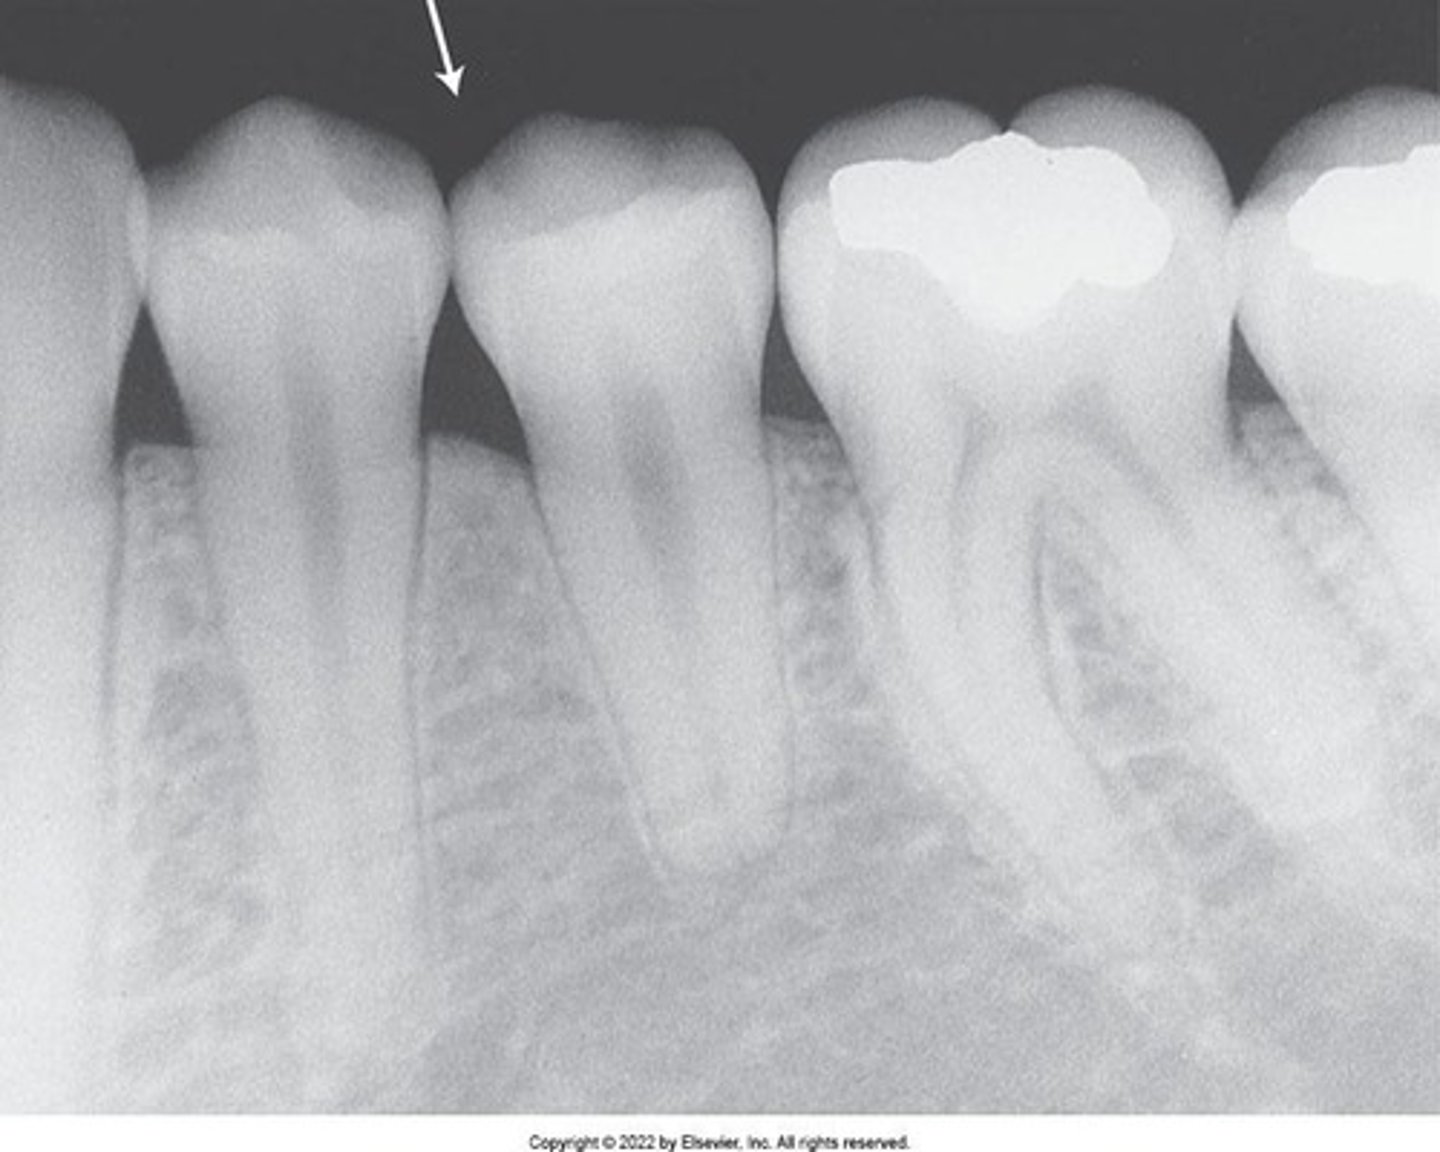

Dental X-Ray Image

A dental image appears as a black and white image or picture with varying shades of gray.

Radiolucent

The portion of the processed image that is dark or black; a structure that appears black on film lacks density.

Radiopaque

The portion of the processed image that appears white; a structure that appears white on film is dense and absorbs or resists passage of the x-ray beam.